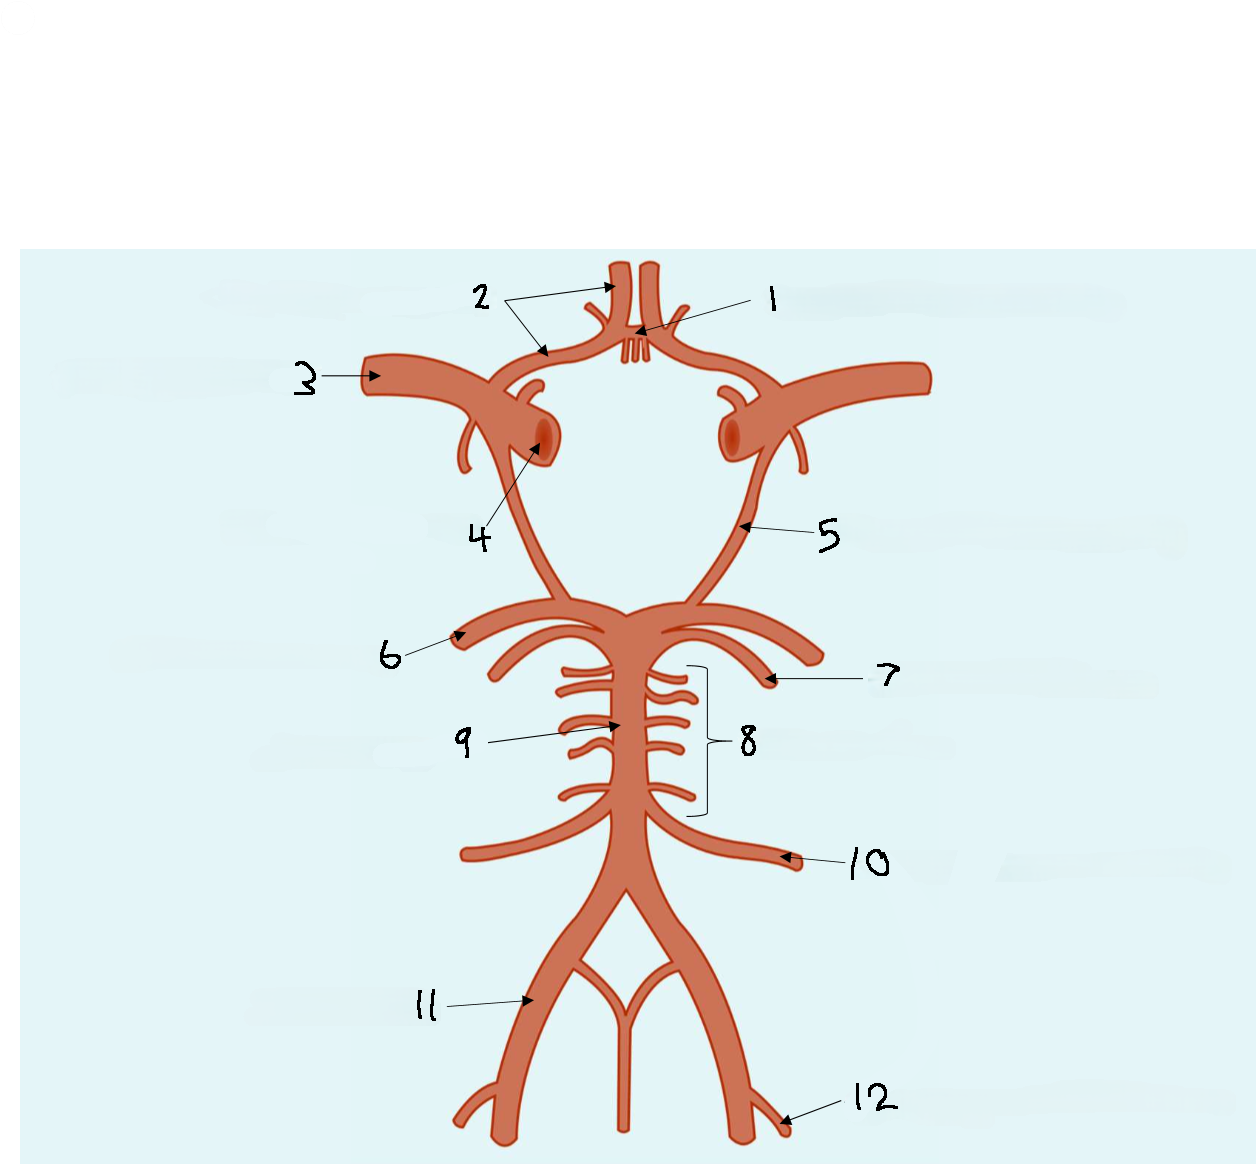

What is 1?

anterior communicating artery

What is 2?

anterior cerebral artery

What is 3?

middle cerebral artery

What is 4?

internal carotid artery

What is 5?

posterior communicating artery

What is 6?

posterior cerebral artery

What is 7?

superior cerebellar artery

What is 8?

pontine arteries

What is 9?

basilar artery

What is 10?

anterior inferior cerebellar artery

What is 11?

vertebral artery

What is 12?

posterior inferior cerebellar artery